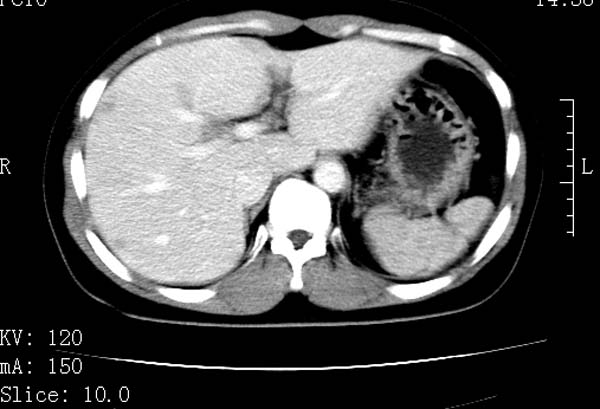

标题: CT22086:女44岁 肝右叶占位增强示巨大血管瘤,门脉期发现小 [打印本页]

标题: CT22086:女44岁 肝右叶占位增强示巨大血管瘤,门脉期发现小

支持肝右叶血管瘤诊断。 小病灶亦考虑血管瘤改变。温习一下:

肝海绵状血管瘤ct平扫常呈均匀低密度,与邻近血管密度相仿。在脂肪肝背景下可呈相对高密度。在增强扫描时,一般早期(动脉期)呈周边结节状或弧形强化,其密度与同层面的血管密度相仿,随着时间延迟向中央渐进性充填,注药后5~7分钟,逐渐扩大至全瘤强化,强化密度逐渐降至稍高于或等于正常肝脏。大的血管瘤往往中央有星形、大的低密度区,可以为纤维化或囊性变所致,纤维化成分可在延迟2 o分钟时完全充填,呈等密度,但囊变区则不会强化。不典型ct表现常见于≤3 cm的小血管瘤。小的血管瘤可以在动脉期即呈全部致密的均匀强化,不呈典型的周边结节状强化表现,但其密度往往较高,与主动脉相仿,在延迟期呈高或等密度。其他不典型的ct表现有:增强扫描强化不明显,呈点状较轻程度的强化,充填慢,可能与供血动脉较细和较大的血管间隙有关以及中央先强化等。

延迟扫描三个病灶都呈等密度改变。肝多发血管瘤,较典型。